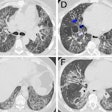

![Images show the pectoralis muscles of a healthy male individual who never smoked (age, 66 years; height, 178 cm; body mass index [BMI, calculated as weight in kilograms divided by height in meters squared], 28.4; number of cigarette pack-years, 0; forced expiratory volume in 1 second [FEV1], 97.6% predicted; FEV1: forced vital capacity [FVC] ratio, 0.71; pectoralis muscle area [PMA], 59.4 cm2; pectoralis muscle volume [PMV], 764 cm3) and a male individual with a smoking history and chronic obstructive pulmonary disorder (COPD) (age, 66 years; height, 178 cm; BMI, 27.5; number of cigarette pack-years, 43.2, FEV1, 48% predicted; FEV1:FVC, 0.56; PMA, 35 cm2; PMV, 480.8 cm3) from the Canadian Cohort Obstructive Lung Disease (i.e., CanCOLD) study. The CT image is shown in the axial plane. The PMV is automatically extracted using the developed deep learning model and overlayed onto the lungs for visual clarity.](https://img.auntminnie.com/mindful/smg/workspaces/default/uploads/2026/03/genkin.25LqljVF0y.jpg?auto=format%2Ccompress&crop=focalpoint&fit=crop&h=112&q=70&w=112)